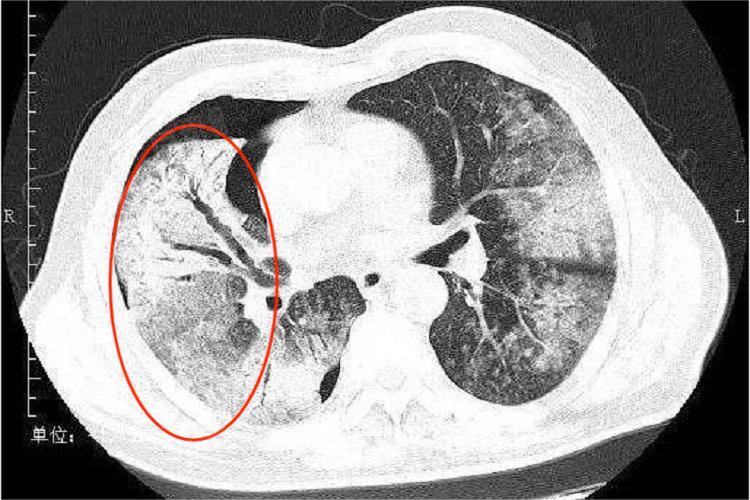

2、支气管扩张症:是一种以支气管永久性扩张为特征的疾病,多由反复的呼吸道感染引起。在高分辨率CT检查中,双轨征是支气管扩张的典型表现之一。扩张的支气管在影像上呈现为与伴行的肺动脉血管类似粗细的管状结构,两者并行排列,形似双轨。这种表现提示支气管壁的弹性纤维和软骨组织受到破坏,导致支气管不可逆地扩张。